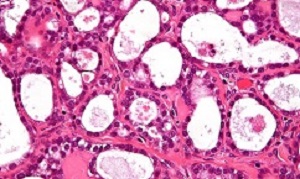

A team at the Institute of Cancer Research created an artificial intelligence (AI) tool that looks for clusters of cells within tumours with misshapen nuclei – the control centres within each cell. Women identified with these clusters of shape-shifting cells had extremely aggressive disease – with only 15% surviving for five years or more, compared with 53% for other patients with the disease.

The researchers found that having misshapen nuclei was an indication that the DNA of cancer cells had become unstable – and believe it could in future help doctors to select the best treatment for each patient.

Cancers with misshapen cell nuclei had hidden weaknesses in their ability to repair DNA, which could make them susceptible to drugs called PARP inhibitors or platinum chemotherapy. The researchers also found that immune cells were not able to move into the clusters of cells with misshapen nuclei, which suggests that cancers with these clusters are better at evading the immune system.

Scientists at The Institute of Cancer Research (ICR) applied their powerful new computer tool to automatically analyse tissue samples from 514 women with ovarian cancer – together looking at nearly 150m cells. The study funded by the ICR itself, used AI to look at the shape and spatial distribution of ovarian cancer cells and their surroundings.

The researchers found that tumours containing clusters of cells whose nuclei varied highly in shape had lower levels of activity of key DNA repair genes, including BRCA1. The test could be used to pick out tumours with lower levels of activity of DNA repair genes, even in cases where the genetic code of the BRCA genes remains intact. These hidden DNA repair defects would be overlooked when only testing for faults in DNA repair genes.

The presence of clusters was associated with even worse prognosis than mutations in the BRCA genes. The team at the ICR – a research institute and a charity – also found that the clusters had higher levels of a protein called galectin-3, which is known to cause key immune cells to die.

How tumor microenvironmental forces shape plasticity of cancer cell morphology is poorly understood. Here, we conduct automated histology image and spatial statistical analyses in 514 high grade serous ovarian samples to define cancer morphological diversification within the spatial context of the microenvironment. Tumor spatial zones, where cancer cell nuclei diversify in shape, are mapped in each tumor. Integration of this spatially explicit analysis with omics and clinical data reveals a relationship between morphological diversification and the dysregulation of DNA repair, loss of nuclear integrity, and increased disease mortality. Within the Immunoreactive subtype, spatial analysis further reveals significantly lower lymphocytic infiltration within diversified zones compared with other tumor zones, suggesting that even immune-hot tumors contain cells capable of immune escape. Our findings support a model whereby a subpopulation of morphologically plastic cancer cells with dysregulated DNA repair promotes ovarian cancer progression through positive selection by immune evasion.